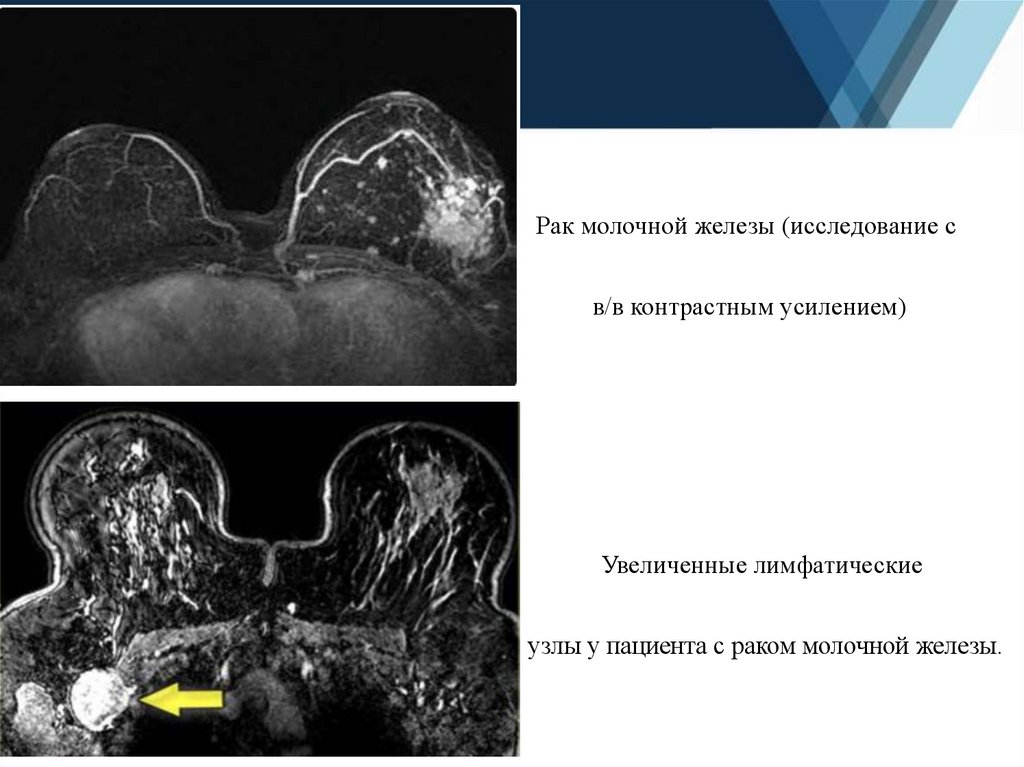

10.

Рак молочной железы (исследование с

в/в контрастным усилением)

Увеличенные лимфатические

узлы у пациента с раком молочной железы.